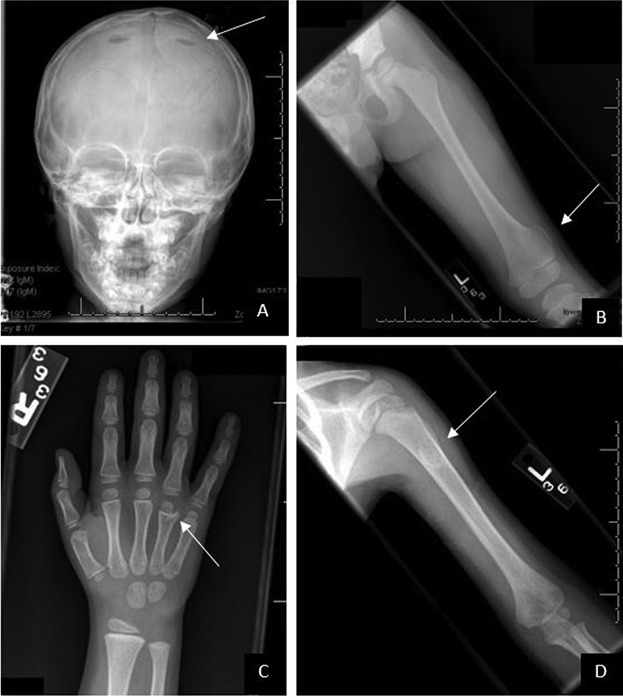

Langerhans cell histiocytosis

A

Most common skeletal manifestations:

Patients may have one or, less commonly, many lesions. The most common locations are the skull and long bones:

skull: ~50%

pelvis: 23%

femur: 17%

ribs: 8% (most common in adults)

humerus: 7%

mandible: 7%

spine

Skull

• solitary or multiple punched out lytic lesions without sclerotic rim

• double contour or beveled edge appearance may be seen due to asymmetrical involvement of the inner and outer tables (hole within a hole) sign 7

• button sequestrum representing residual bone

• geographic skull